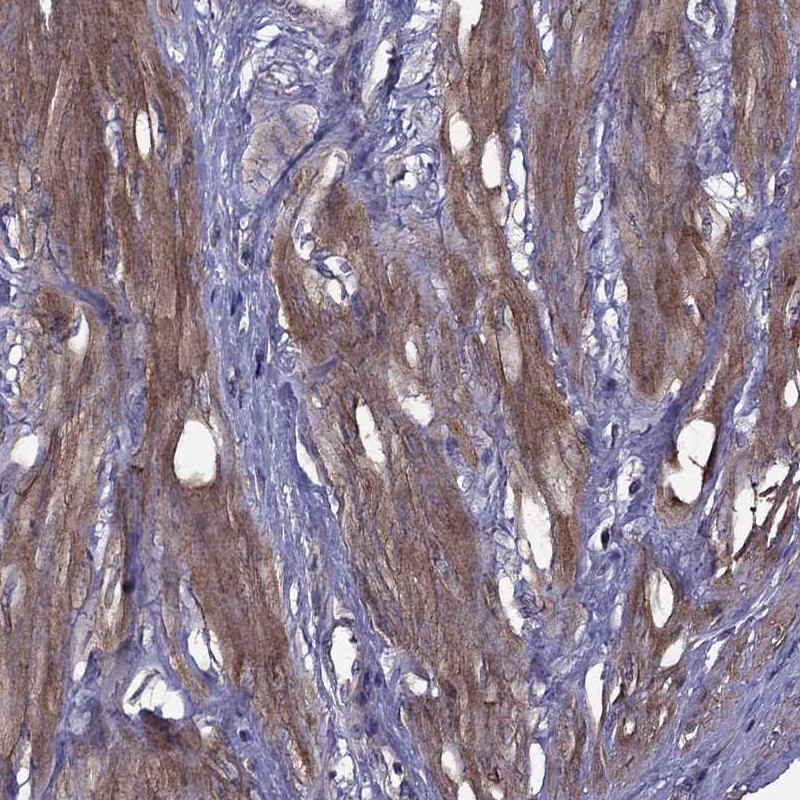

Immunohistochemistry analysis in human smooth muscle and pancreas tissues using Anti-ITGB1 antibody. Corresponding ITGB1 RNA-seq data are presented for the same tissues.